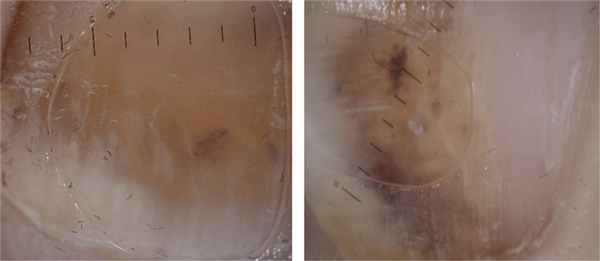

При наличии рваной раны ногтевого ложа или перелома кончика дистальной фаланги удаляется ноготь. Если перелома нет, перфорируют ногтевую пластинку над образовавшейся гематомой с помощью аппарата для прижигания или иглы путем вращения. При достижении адекватного дренирования, подногтевая гематома удаляется через проделанное отверстие при нажатии на ногтевую пластинку вокруг него.

- Дренирование гематомы. Ногтевая пластина над гематомой прокалывается иглой или прожигается термокаутером. Отток крови через небольшое отверстие приводит к снижению давления на ткани, уменьшению интенсивности болевых ощущений. Дренированная подногтевая гематома быстрее рассасывается, что значимо для пациентов, которым важно не иметь косметических дефектов на руках.